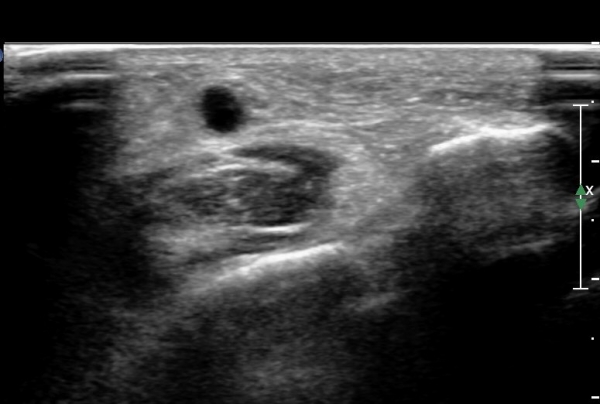

¾Æ·§´Ù¸® ¿ÜÃø Ⱦ´Ü¸é°Ë»ç¿¡¼ Àåºñ°ñ±Ù°ú ¹ß°¡¶ô½ÅÀü±Ù »çÀÌ¿¡¼ õºñ°ñ½Å°æÀÌ Á¤»óÀûÀ¸·Î °üÂûµÈ´Ù(»çÁø 1, , 2, 3, 4, 5).